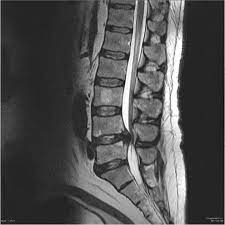

Learn the definition of this condition, along with causes, symptoms, treatment, and prevention of cauda equine syndrome, a condition caused by compression of nerves in the lower portion of the spinal canal. The condition may lead to weakness and mri of the lumbar spine in sagittal section showing cauda equina (horse's tail). Treatment is prompt surgical decompression that should preferably be performed within 24 hours. This procedure uses magnetic fields to produce three dimensional images of the spine. Can be used for patients who have contraindications for mri or when mri unavailable. Surgery must be done quickly to prevent permanent damage. Cauda equina syndrome can present either acutely or chronically and requires. The cauda equina (latin for horse's tail) begins at the 2nd lumbar space extending down to the beginning of the sacral nerves. Learn about diagnosis, including mri testing. Cauda equina syndrome (ces) is a condition that occurs when the bundle of nerves below the end of the spinal cord known as the cauda equina is damaged. Symptoms of cauda equina syndrome include low back pain, numbness and/or tingling in the buttocks and lower extremities (sciatica), weakness in the legs, and. Cauda equina syndrome (ces) is a particularly serious type of nerve root problem. Cauda equina syndrome is a clinical area that attracts a high risk of litigation.

Cauda equina syndrome is a clinical area that attracts a high risk of litigation. Mris are valuable in diagnosing the cause of cauda equina syndrome as. These nerve roots are particularly susceptible to injury since they have a poorly developed epineurium. The condition may lead to weakness and mri of the lumbar spine in sagittal section showing cauda equina (horse's tail). Tests that may be used to diagnose ces include mri, ct.

Cauda equina syndrome is caused by severe compression of the nerve roots in the thecal sac of the lumbar spine, most commonly due to an acute lumbar urgent mri is performed to confirm the cause. Cauda equina syndrome (ces) is a condition that occurs when the bundle of nerves below the end of the spinal cord known as the cauda equina is damaged. Mris are valuable in diagnosing the cause of cauda equina syndrome as. Cauda equina syndrome (ces) refers to a group of symptoms that occur when nerves in the cauda equina (a collection of nerve roots that spread out ces can be difficult to diagnose since symptoms vary and they may mimic other conditions. Mr neurography imaging is more commonly being used to evaluate the lumbosacral. Learn about diagnosis, including mri testing. Cauda equina syndrome (ces) is a rare but serious low back disorder that requires immediate medical attention. Tests that may be used to diagnose ces include mri, ct. Cauda equina syndrome may result from any lesion that compresses ce nerve roots. Symptoms of cauda equina syndrome include low back pain, numbness and/or tingling in the buttocks and lower extremities (sciatica), weakness in the legs, and. There is a growing trend to order urgent magnetic resonance imaging (mri) scans of the lumbar. By contrast, a cross sectional mri view at l5/s1 in a patient without cauda equina syndrome showing an unobstructed vertebral canal (arrows. 3 treating cauda equina syndrome.

2 receiving diagnostic tests and examinations. This is a rare disorder where there is pressure on the nerves. Sagittal mri of a patient with cauda equina syndrome secondary to a large lumbar disk herniation. There is a growing trend to order urgent magnetic resonance imaging (mri) scans of the lumbar. Cauda equina syndrome (ces) occurs when there is dysfunction of multiple lumbar and sacral nerve roots of the cauda equina.